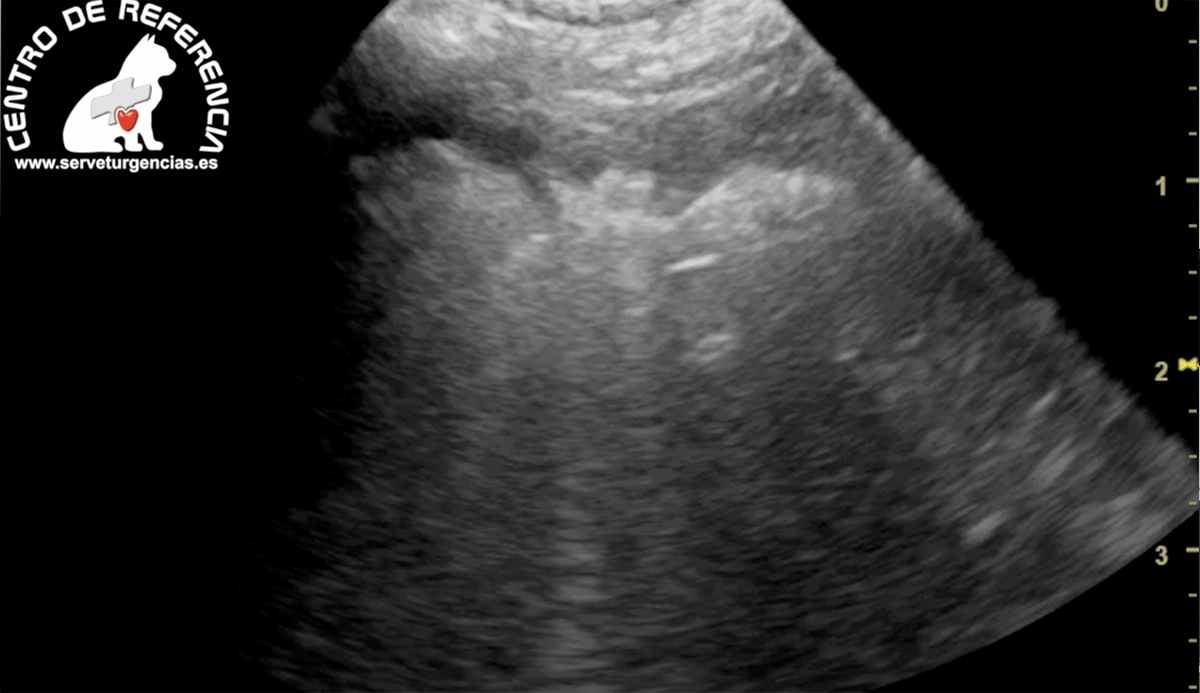

El edema pulmonar ocurre cuando se acumula líquido en los pulmonares, esto dificulta la respiración. La presencia de liquido en los pulmones interfiere con el intercambio de gases y puede causa insuficiencia respiratoria.

El tratamiento inicial del edema pulmonar se enfoca en mejorar la función respiratoria y disminuir la cantidad de líquido presente en el pulmón. Generalmente incluye proporcionar oxígeno, diuréticos y en casos más graves ventilación asistida.

El Servet urgencias el edema pulmonar casi siempre se trata en la UCI. Al animal se le administra oxígeno a través de un helmet (casco que cubre toda cabeza) o se colocan pequeños tubos de plástico en la nariz. En casos más graves se puede colocar un tubo de respiración en la tráquea y conectarlo a un respirador si el animal no puede respirar bien por su cuenta.

La causa del edema debe identificarse y tratarse rápidamente.